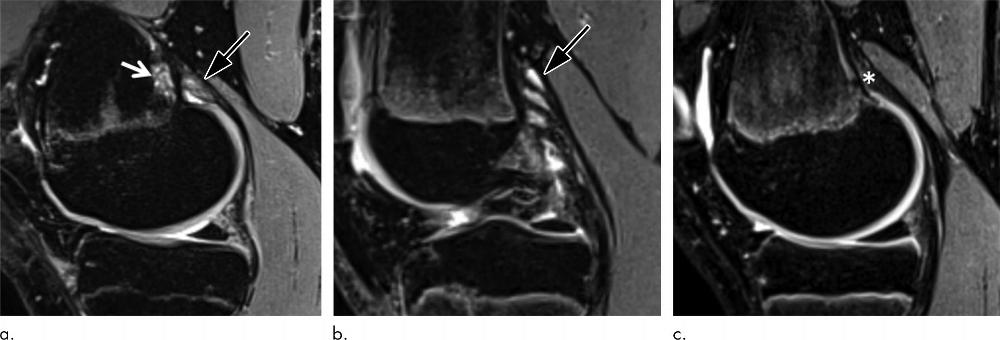

Figure 1. (a) Sagittal fat-suppressed proton density–weighted MRI scan in a 14-year-old male control participant with distal femoral cortical irregularity (DFCI) (arrow) at the level of the tendon attachment of the medial head of the gastrocnemius muscle (MHG) (*). (b) Sagittal illustration with DFCI (arrow) at the MHG attachment (*). The size of the DFCI is determined as the greatest anteroposterior diameter (solid line in a and b). Note that the bandlike hyperintense periosteal stratum osteogenicum (in between red dotted lines in a and b) is not included in the measurement.